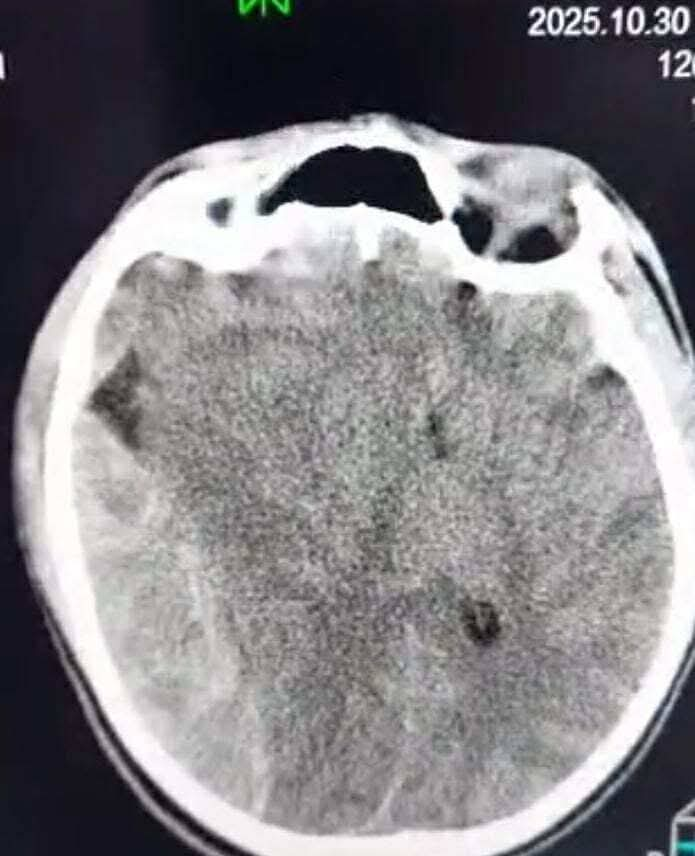

وفور وصول المريض بسيارة الإسعاف إلى قسم الإستقبال والطوارئ، توقفت عضلة القلب، ليتم على الفور تنفيذ إجراءات الإنعاش القلبي الرئوي من قبل فريق الطوارئ لإنقاذ حياته. وبعد استقرار الحالة، أُجريت الفحوصات الطبية العاجلة التي أظهرت وجود نزيف شديد خارج الأم الجافية وانحدار في مستوى المخ نحو الجانب الأيسر.